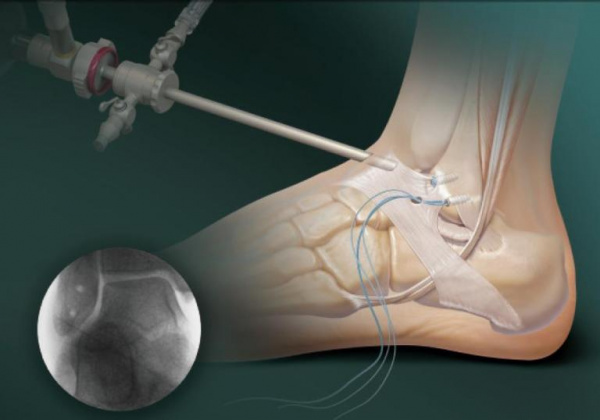

- Ортопедические операции. При гнойном артрите выполняется артроскопия с дренированием полости голеностопного сустава. При стойком рецидивирующем течении ревматоидного артрита показана артроскопическая синовэктомия. При тяжелых деформирующих формах заболевания требуется проведение артроскопического артродеза голеностопного сустава или эндопротезирования.